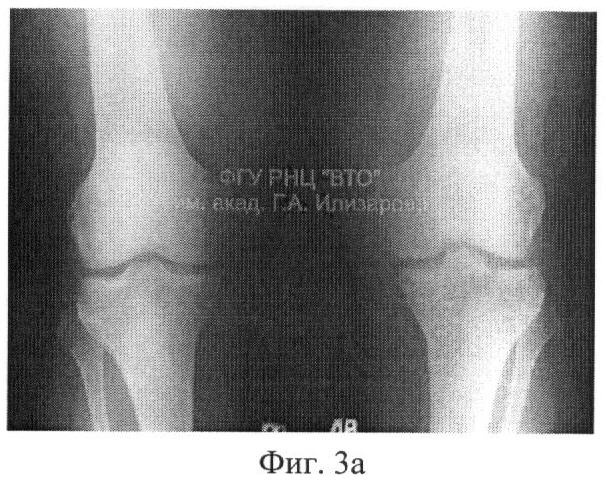

Фиг.1 – рентгенограмма коленного сустава больного Р. до лечения;

Фиг.3 – рентгенограмма коленного сустава после лечения; а – прямая проекция,

б – боковая проекция.

На второй день после операции больному назначали ходьбу с помощью костылей с постепенно возрастающей нагрузкой на оперированную конечность. Через две недели назначали курс ЛФК с активно-пассивной разработкой движений в коленном суставе, которую продолжали в течение 51 дня до консолидации перелома (фиг.3). На момент выписки амплитуда активных движений в коленном суставе составляла: при сгибании – до 90 градусов, при разгибании – полное; на контрольно осмотре через 1 год – в пределах нормы.